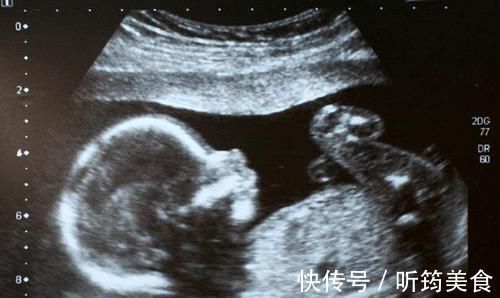

产检一切正常,胎儿出生之后却是畸形由于工作的关系,再加上眼光比较高,王敏结婚时间比较晚,一直到33岁才结婚,第二年怀孕。

身为高知识分子,王敏很清楚自己这个年龄怀孕属于高危活动,毕竟年龄上离大龄产妇仅一步之遥,众所周知,大龄产妇不论是母体还是宝宝都有很大可能出现问题。

在这样的情况下,王敏极度重视胎儿的健康状况,平日里这个不敢吃,那个不敢碰,而且没事就去做产检。发展到后期,就连她爱人都觉得妻子有点神经质,毕竟就算是正常人一直做体检,迟早也会出现问题,何况是身体处于特殊时期的孕妇?

面对爱人的质疑,王敏很冷静,她说自己很清楚自己在做什么,这并不是发疯,也不是没事找事。在她看来,虽然经常去产检显得不太正常,但至少目前为止,医生没有说做检查会危及胎儿,但大龄产妇的高危性却已经得到了公认,她宁可相信已经得到证实的东西。

本来一切都很好,产检结果正常,王敏的身体状况也没异状,就在全家人等着庆祝时,让所有人都想不到的情况发生了——居然是畸形儿!